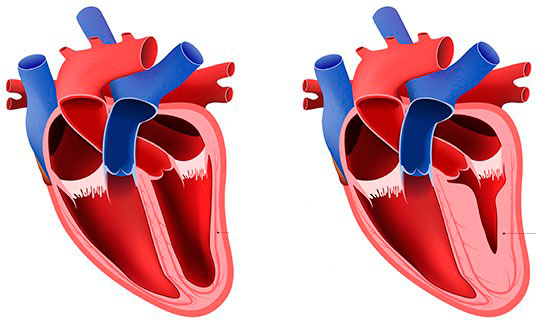

O que são ventrículos?

São as partes maiores e mais fortes do coração, as partes que bombeiam o sangue para a

circulação.

O ventrículo direito envia sangue para os pulmões.

O ventrículo esquerdo envia sangue para o restante do corpo.

O que é septo interventricular?

É uma estrutura que separa os ventrículos direito e esquerdo.